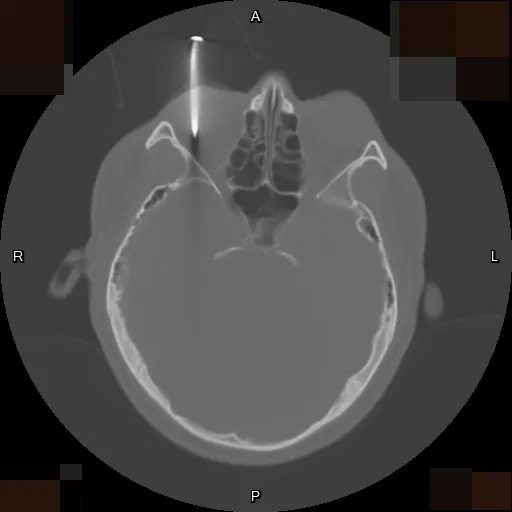

電腦斷層影像可看到男子右眼插著一根釘子,直達眼球的後方。李學宇醫師提供